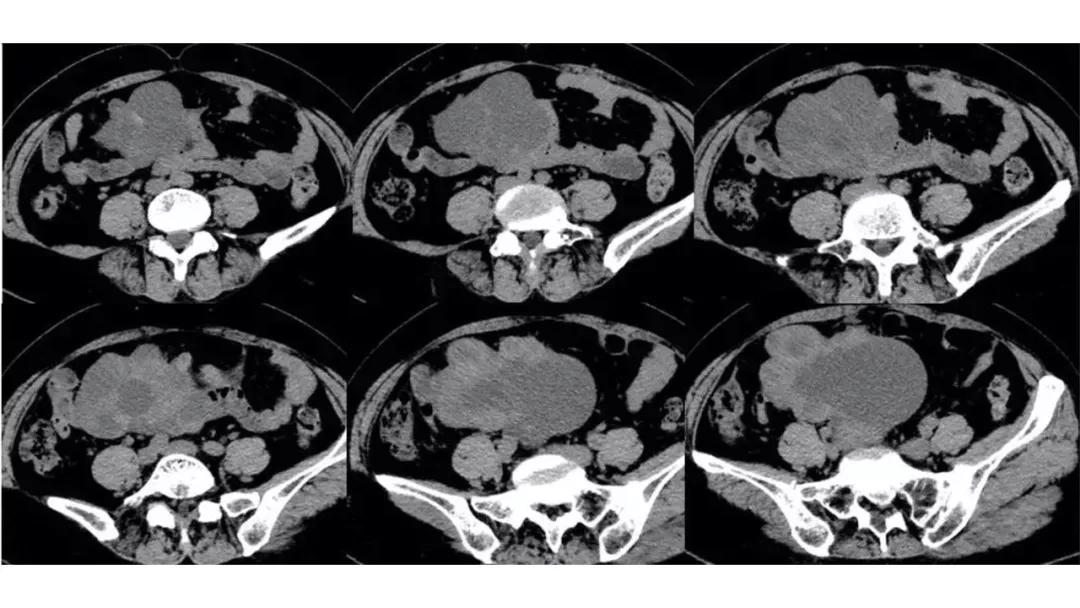

病例4 女,32岁,以“月经量增多伴经期延长半年。”

缘于患者入院前半年无明显诱因出现月经量增多,卫生巾由原来3包余增至5包不等,伴血块,经期由原来7天延长至10-15天不等,无痛经,无月经周期改变,无阴道异常排液,无畏冷、发热,无头晕、乏力等不适,未重视,未诊治。期间症状持续。2月前就诊我院,查彩超示:“子宫体大小约5.7*5.3*4.6cm,内膜厚约0.6cm,回声不均,左卵巢旁探及大小约4.2*3.5cm低回声区。”建议治疗,患者及家属表示考虑。期间症状持续,今就诊我科门诊,要求住院手术治疗,无腹痛等不适,门诊拟“卵巢囊肿”收住入院。既往史:2007年剖宫产一次,术顺。月经史:15 7/25 lmp2018.05.14,量中,无痛经。婚育史:已婚,1-0-3-1,末孕2007年剖宫产娩一男婴,儿子及丈夫体健。个人史、家族史均无特殊。

TCT:见少许非典型细胞;(2018.03.26)HPV:均阴性;

2018-05-28 血常规五分类:白细胞 8.2(10^9/L),中性粒细胞百分比 65.80(%),血红蛋白 108(g/L),血小板 359(10^9/L);凝血功能、肝肾功能电解质、尿常规大致正常;乙肝两对半加丙肝均阴性;

尿HCG 阴性;RPR 阴性,TPPA 阴性,HIV抗体 阴性;

CA125 335.5(U/mL);2018-05-30 彩超:子宫宫体大小约5.6㎝×6.3㎝×4.9㎝,形态正常,宫壁回声欠均,内膜厚约1.8cm,回声不均。CDFI:子宫内未见明显异常彩色血流信号。左附件区探及一混合回声团块,大小约9.8㎝×7.9㎝,CDFI:其实性部分可见少许彩色血流信号。右附件区未见明显包块回声。

病理:卵巢子宫内膜样癌